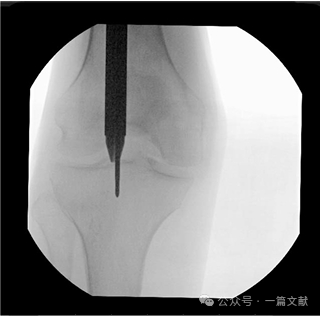

图6,胫骨远端导针的最佳位置:导丝的最佳终点应位于踝穴位,关节面中点稍偏外侧的位置。如下图:

这种方法有助于确保髓内钉的正确位置,避免近端突出。